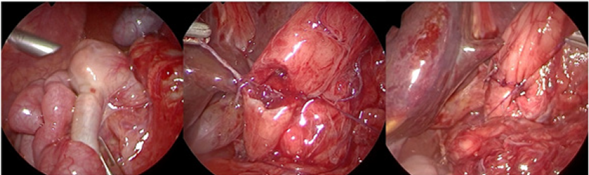

En el primer paciente se utilizó la técnica descrita por Kimura2,5,11, realizando una duodenotomía transversal proximal a la membrana y otra longitudinal distal a ésta, con duodeno-duodenoanastomosis en forma de diamante (Figura 4).

Figura 4 Intraoperatorio paciente 1, zona de transición, sutura de la cara posterior y sutura completa.